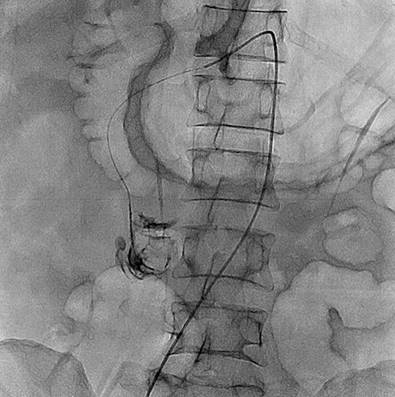

Durante los tres primeros días de hospitalización persistió con hematoquecia, hipotensión y anemización grave que no corrigió a pesar de ser politransfundido, por lo que se solicitó arteriografía mesentérica, en la cual no se encontraron lesiones que explicaran el sangrado. El paciente se tornó inestable hemodinámicamente, por lo que fue trasladado a la unidad de cuidados intensivos (UCI) con requerimiento transfusional, soporte vasopresor y ventilación mecánica invasiva. Además, tenía un cuadro de hematemesis con necesidad de endoscopia de vías digestivas altas que reportó una “angiodisplasia de bulbo duodenal, la cual recibió escleroterapia”. Por la persistencia de inestabilidad hemodinámica, sangrado digestivo bajo y anemización grave, se realizó una angiotomografía abdominal, en la que se observó una “dilatación en el segmento intestinal delgado ileal, que podría corresponder a un divertículo de Meckel, con extravasación del medio de contraste a través de este segmento” (Figura 1), por lo que se le realizó una embolización selectiva por medio de arteriografía (Figuras 2 y 3).

Figura 2 Embolización angiográfica del divertículo yeyunal, en la que se resalta una figura quística compatible con divertículo yeyunal. Fuente: Servicio Hemodinamia, Hospital Comuneros. Seleccionada por autores.

Figura 3 Embolización angiográfica del divertículo. Fuente: Servicio Hemodinamia, Hospital Comuneros. Seleccionada por autores.